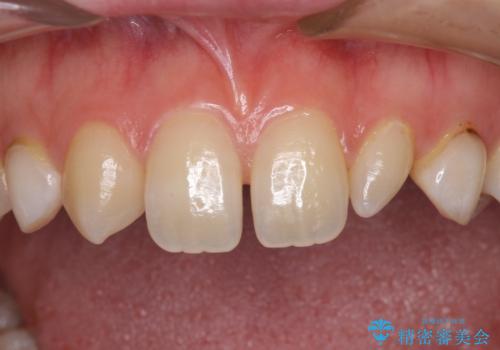

前歯の奇形歯 オールセラミッククラウンによる審美歯科治療

- 前歯の奇形や欠損、乳歯残存などによる審美障害を気にして来院された患者様です。

正中の隙間は矯正治療により閉じ、左右の4歯はオールセラミッククラウンにて補綴することとしました。